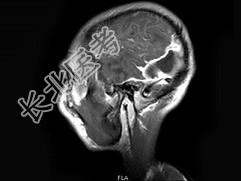

- 单项选择题男,30岁, 寒战,高热伴头痛, 呕吐10天,头颅MRI平扫及增强扫描见颅内不规则环形强化, 应诊断为 ( )

A、化脓性脑膜脑炎并脑脓肿形成

B、结核性脑膜脑炎并结核瘤形成

C、脑膜及颅内转移瘤

D、星形细胞瘤

E、未见异常